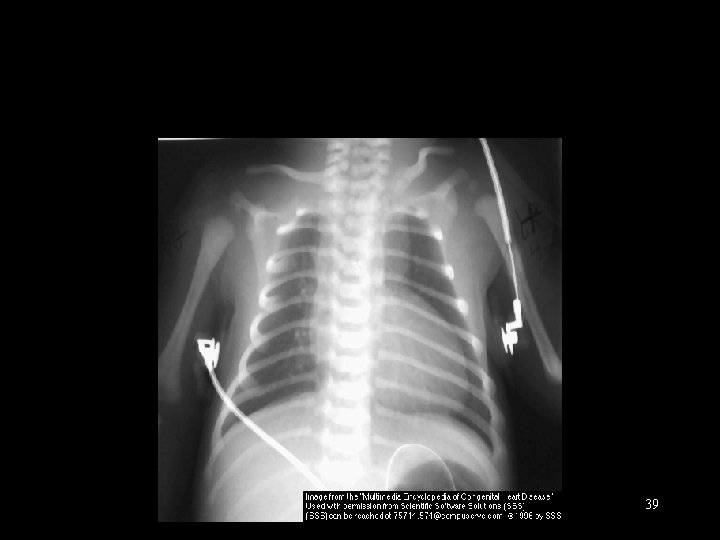

Inadequate Mixing Lesions § § § § Cyanosis, often profound Mild tachypnea Normal pulses Single heart sound Murmur ABG: marked hypoxemia, + acidosis CXR: cardiomegaly, normal or increased PBF 38

39

d - Transposition of the Great Vessels 40

Transposition of Great Arteries Mixing at PFO and PDA